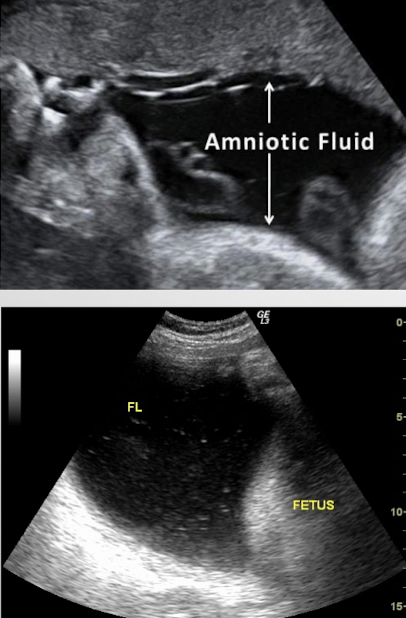

amniotic fluid

fluid surrounding fetus within amnion

plays vital role in fetal growth and allows fetus to move freely

produced by umbilical cord, membranes, lungs, skin, kidneys, and mostly by urinary tract

SONO: amniotic fluid

generally echo-free

can sometimes see tiny echogenic particles

blood, normal variant, vernix caseosa, meconium

presence of a dense collection, or sludge, could indicate infection